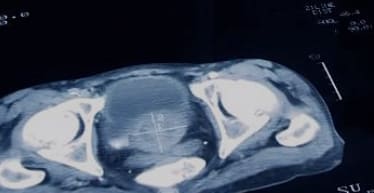

- 전립선 비대증은 나이가 들면서 전립선이 점차 커져서 요도를 압박하고 소변을 보기 어렵게 만드는 질환입니다.

- 전립선은 남성의 생식기관으로, 방광 바로 밑에 위치하며 소변과 정액의 배출을 돕습니다.

- 진단은 의사가 문진, 신체검사, 소변검사, 혈액검사, 초음파검사 등을 통해 진행합니다.